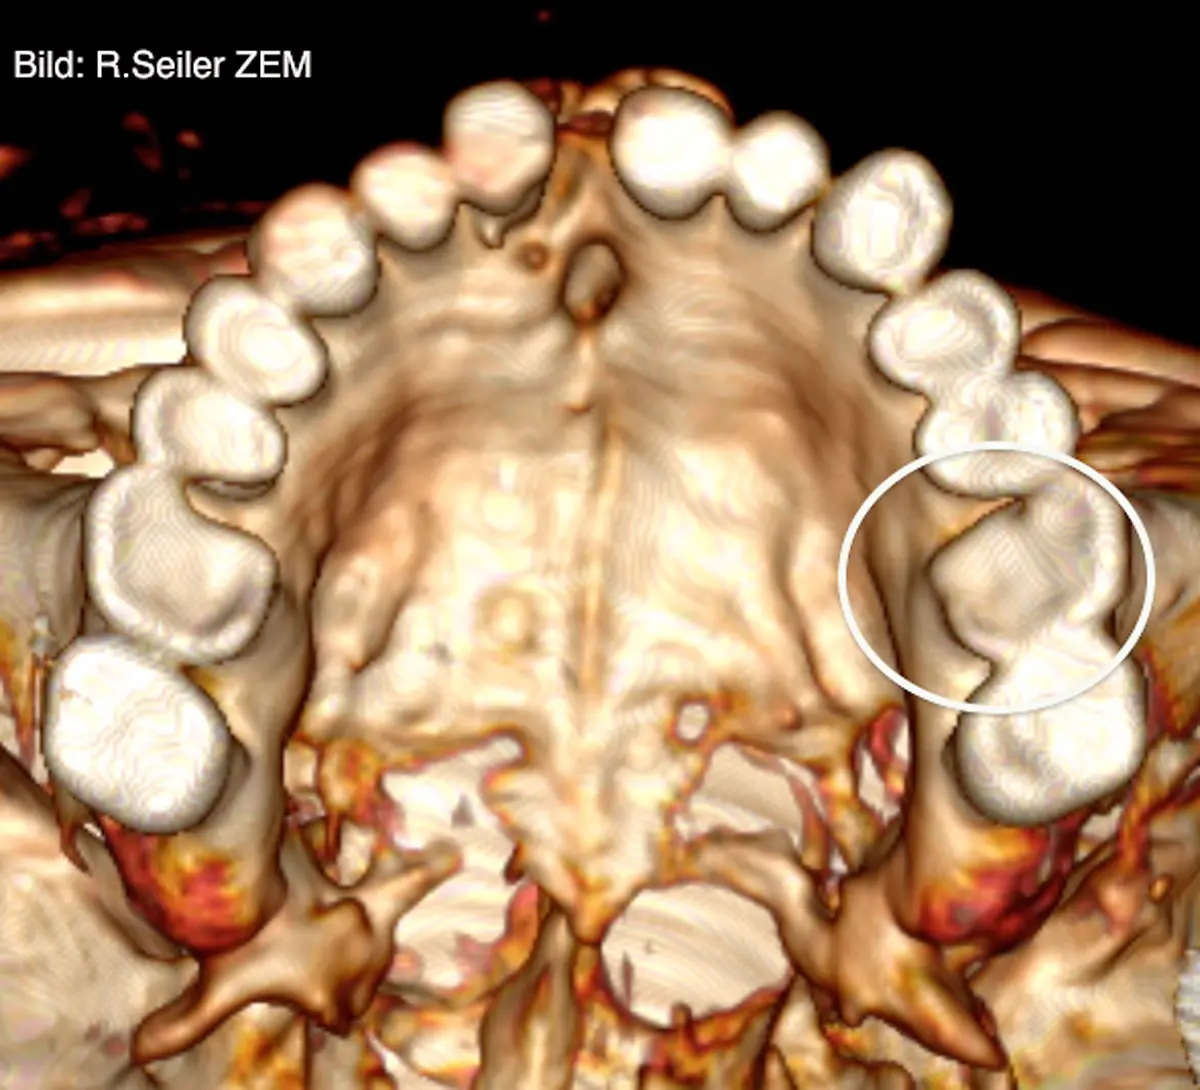

Er war ein Revolutionär der Medizintechnik: Der Physiker Wilhelm Conrad Röntgen entdeckte 1895 zufällig die X-Strahlen, was nicht nur für die Diagnostik in der Medizin ein Meilenstein war. Später wurden die Strahlen und das Verfahren nach ihm benannt. Röntgen starb vor 100 Jahren in München.